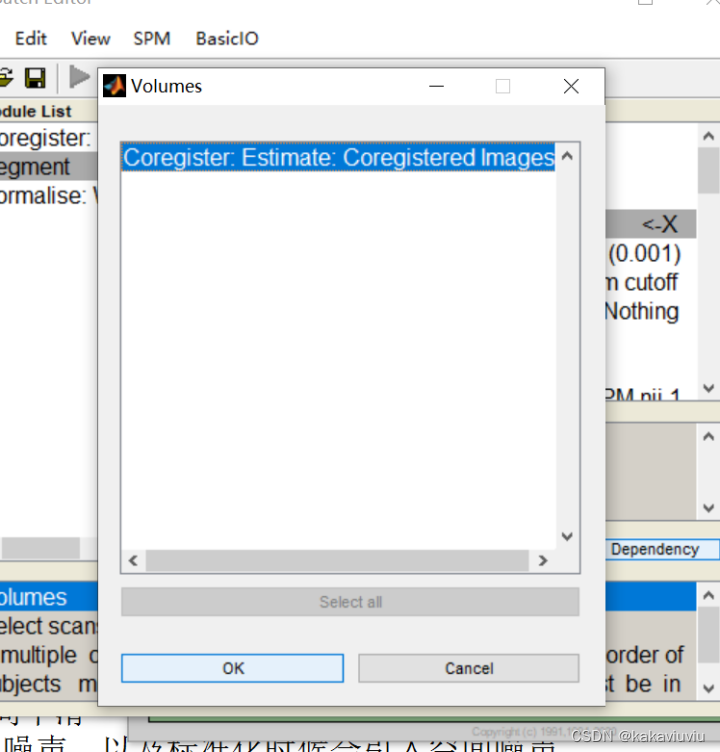

1.个体T1---线性---->配准到个体fMRI的个体T1(Coregister(Estimate))

T1选为source image